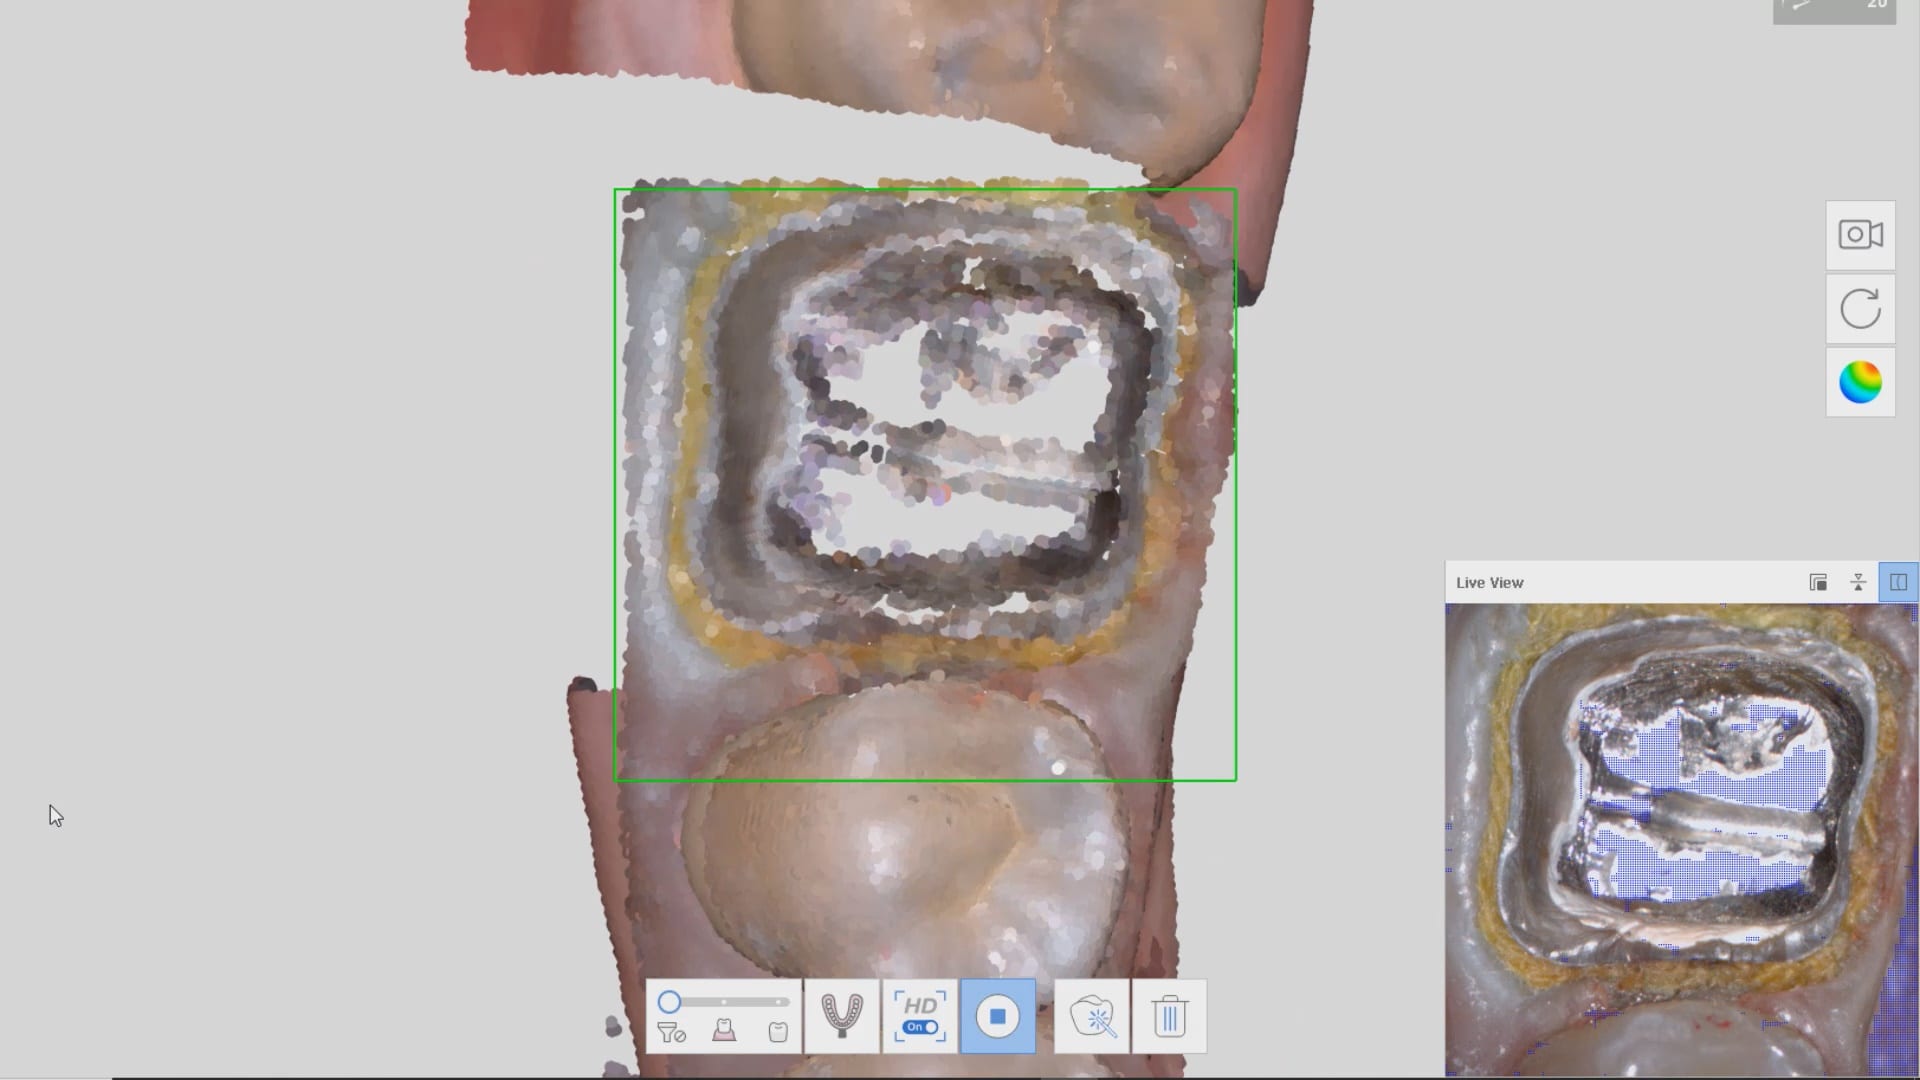

Imaging a deep margin with the Medit i500

In this clinical video we demonstrate how to scan a molar preparation for the replacement of a crown with recurrent decay and open margins. The molar was root canal treated and the tissue was inflamed. the preparation was imaged and a temporary was fabricated to allow the tissue to heal properly.

The main point of this video is to show how to capture the contacts of the adjacent teeth and the deep marings